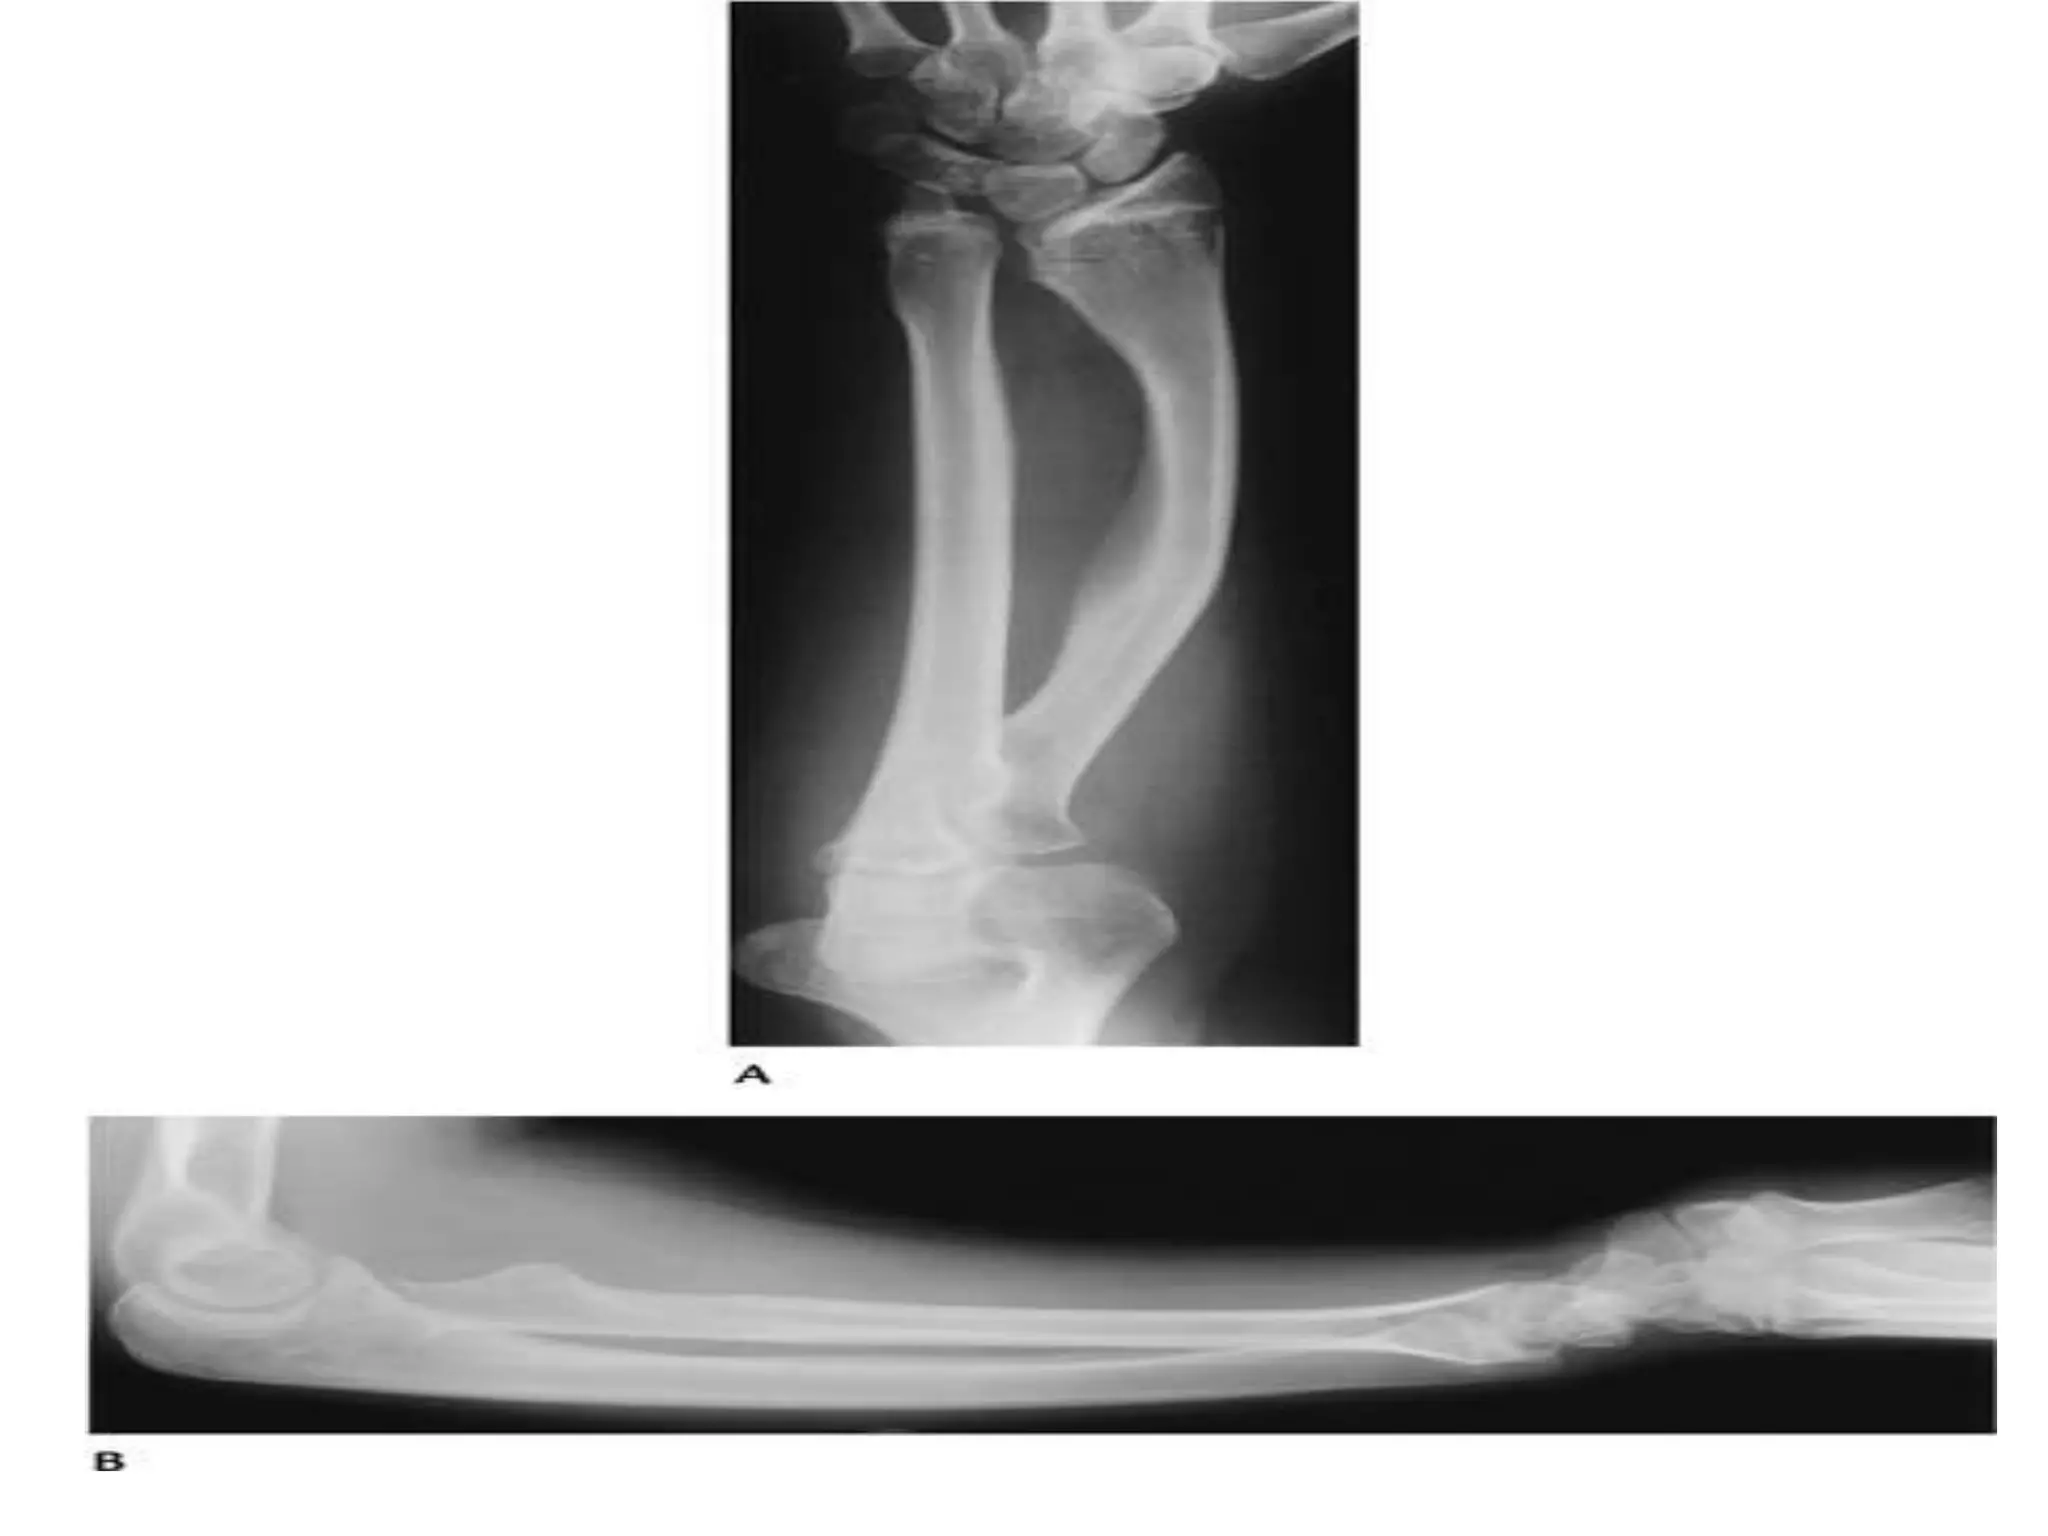

Dyschondrodystosis

Disproportionate shortening of limbs.

Middle segments (forearm/leg) are

affected.

stature reduced but not as in

achondroplasia.

Xray: short forearm/leg

bow radius

madelung’s deformity of

wrist

Dyschondrodystosis Disproportionate shortening oflimbs. Middle segments (forearm/leg) are affected. stature reduced but not as in achondroplasia. Xray: short forearm/leg bow radius madelung’s deformity of wrist Treatment: operative